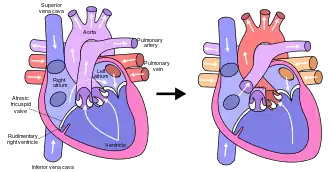

Fontan procedure for tricuspid atresia | |

The Fontan procedure or Fontan–Kreutzer procedure is a palliative surgical procedure used in children with univentricular hearts. It involves diverting the venous blood from the inferior vena cava (IVC) and superior vena cava (SVC) to the pulmonary arteries. The procedure varies for differing congenital heart pathologies. For example in tricuspid atresia, the procedure can be done where the blood does not pass through the morphologic right ventricle; i.e., the systemic and pulmonary circulations are placed in series with the functional single ventricle. Whereas in hypoplastic left heart syndrome, the heart is more reliant on the more functional right ventricle to provide blood flow to the systemic circulation. The procedure was initially performed in 1968 by Francis Fontan and Eugene Baudet from Bordeaux, France, published in 1971, simultaneously described in 1971 by Guillermo Kreutzer from Buenos Aires, Argentina, and finally published in 1973.[1][2]

The Fontan Kreutzer procedure is used in pediatric patients who possess only a single functional ventricle, either due to lack of a heart valve (e.g. tricuspid or mitral atresia), an abnormality of the pumping ability of the heart (e.g. hypoplastic left heart syndrome or hypoplastic right heart syndrome), or a complex congenital heart disease where a bi-ventricular repair is impossible or inadvisable. The surgery allows blood to be delivered to the lungs via central venous pressure rather than via the right ventricle.[3] Patients typically present as neonates with cyanosis or congestive heart failure.[4] Fontan completion is usually carried out when the patient is 2–5 years of age, but is also performed before 2 years of age.[5][6]